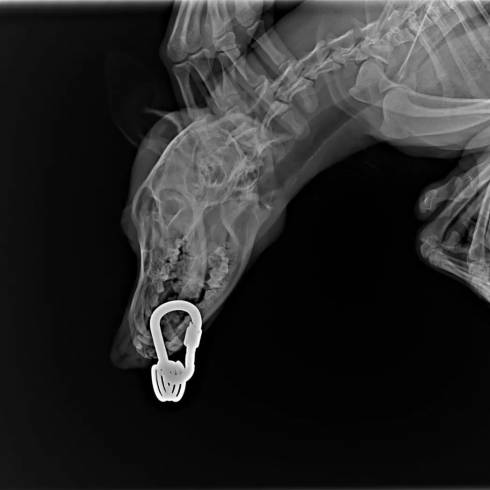

Зоозащитники Караганды: живодеров, пробивших нижнюю челюсть щенку карабином, не найдут

В Караганде неизвестные живодеры пробили нижнюю челюсть 4-месячному щенку карабином и повредили ему лапы

Свидетелями ужасающей жестокости стали карагандинские защитники животных. Вчера в приют "У рыжего кота" неравнодушная жительница города принесла щенка со страшными травмами. Малышу всего 3-4 месяца отроду. Неустановленные преступники насквозь пробили щенку нижнюю челюсть альпинистким карабином и защелкнули его. Трудно представить, какую боль и страх перенесло животное.

Щенок Щен, которому живодеры пробили нижнюю челюсть карабином, обрел семью и дом

У страшной истории издевательства над беззащитным животным - хорошая концовка. Щена забрала домой к себе семья из Караганды.

Щенок, которому пробили нижнюю челюсть карабином, пошел на поправку и готовится к выписке

Хорошая новость от зоозащитников. Щенок Щен пошел на поправку.